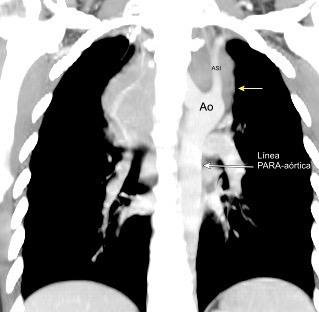

Visible en el adulto normal por interfase de la pared externa de la aorta con el aire del LII.

Causas de alteración

Normal

Patología aórtica Disección/ Aneurisma Úlcera ateroesclerótica

Adenopatías/ Ca. de Pulmón Hematoma Patología del LII

Marano R et al .Cardiac Silhouette Findings and Mediastinal Lines and Stripes. Chest 2011

30 años

Borramiento de la banda PARA-aórtica por AdenoCa. de LII, no visible en 2005

Colapso de LII. TC: secreciones bronquiales.

Endoscopia tapón mucopurulento extraído

Borramiento parcial por Ca. epidermoide.